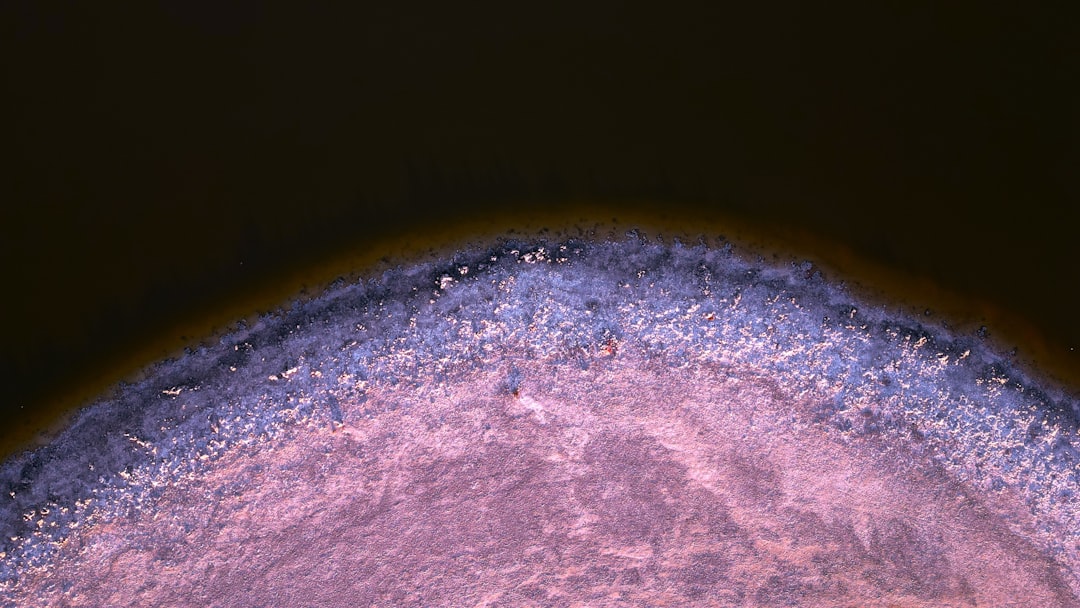

이 치료 기법은 줄기세포를 활용해 신경 세포를 재생하는 것입니다. 줄기세포는 다양한 세포로 분화할 수 있는 능력을 가지고 있어, 손상된 세포를 대체할 수 있는 가능성을 지니고 있습니다. 따라서 파킨슨 줄기세포 치료는 황금 같은 기회를 제공할 수 있는 혁신적인 접근법으로 주목받고 있습니다.

줄기세포가 신경 세포로 변해 손상된 뉴런을 대체하는 과정은 복잡합니다. 이 과정은 여러 단계를 거쳐 진행되며, 줄기세포가 적절한 환경에서 융합하고 기능을 할 수 있는지에 대한 연구가 필요합니다. 또한, 이 치료의 장기 효과에 대한 연구도 진행되고 있으며, 이를 통해 환자들에게 보다 안전하고 효과적인 치료법을 제공할 수 있을 것입니다.